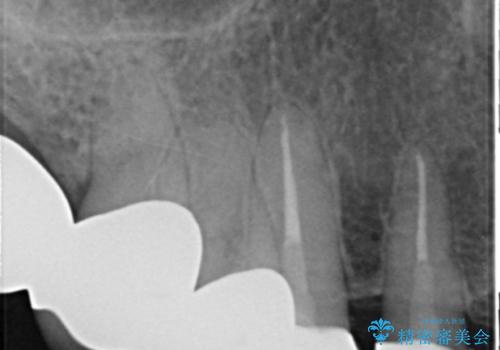

上の前歯6本はメタルボンドクラウン(内側が金属の被せ物)で補綴されており、顕著な歯肉退縮を認めました。

被せ物を除去したところ根管治療後の処置が不十分であったため、ファイバーコア(金属を用いない強くてしなやか材質の土台)を植立したのち、ジルコニアセラミッククラウンによる治療を行いました。